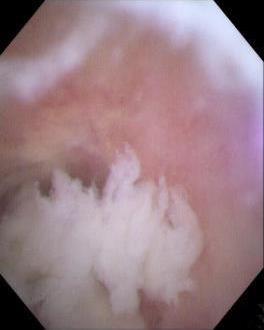

摘要:目的 探讨一次性子母胆道镜辅助内镜逆行阑尾炎治疗术在急性非复杂性阑尾炎治疗中的诊断和治疗价值。方法 回顾性分析2022年9月-2024年9月该院内镜中心通过一次性子母胆道镜辅助内镜逆行阑尾炎治疗术治疗的39例急性非复杂性阑尾炎患者的临床资料,观察内镜下表现、子母网篮取石率、阑尾支架置入率、技术成功率、临床成功率、手术时间、住院时间、并发症发生率和术后6 h视觉模拟评分法(VAS)评分,以及术后24 h炎症指标。结果 28例(71.8%)患者结肠镜下阑尾开口可见充血和水肿,10例(25.6%)患者结肠镜下阑尾开口可见脓液流出,32例(82.1%)患者子镜下阑尾腔内可见大量脓液,20例(51.3%)患者子镜下阑尾腔内可见粪石;一次性子母胆道镜辅助内镜逆行阑尾炎治疗术的技术成功率为100.0%(39/39);手术时间(21.08±7.49)min;住院时间(3.97±2.08)d;8例(20.5%)患者行内镜下子母网篮取石术;14例(35.9%)患者行阑尾支架置入术。临床成功率为97.4%(38/39),1例患者术后临床症状和炎症指标未缓解,转外科行阑尾切除术。38例患者术后6 h的VAS评分 < 3分,腹痛症状明显缓解;术后24 h白细胞计数和中性粒细胞百分比较术前明显下降,差异均有统计学意义(P < 0.05);39例患者均未发生并发症;术后随访(5.94±4.03)个月,3例(7.7%)出现复发。结论 一次性子母胆道镜辅助内镜逆行阑尾炎治疗术诊断和治疗急性非复杂性阑尾炎,安全且有效,值得临床推广应用。